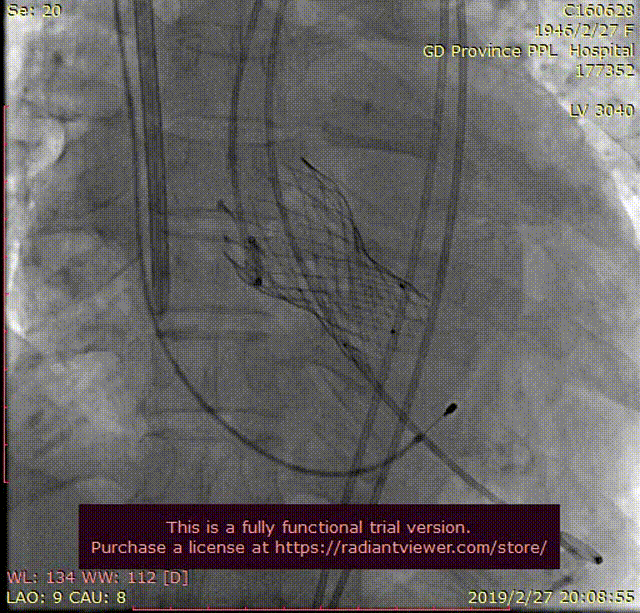

植入巴德ZVL10060支架

复查造影